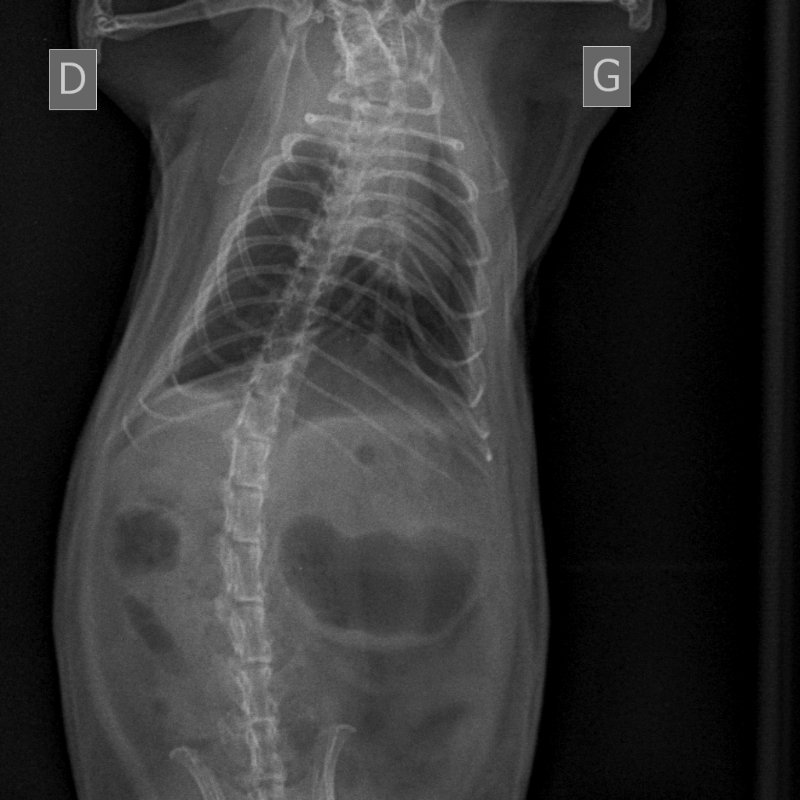

Début avril, comme vu plus tôt, 10 jours de doxycycline, 5mg/kg/12h, en PO pour Koba suite à symptômes respis avec perte de poids.

Il y avait du mieux donc on a arrêté au bout de 10 jours.

Et puis fin avril sa respiration est devenue accélérée de façon flagrante, avec quelques rares bruits respiratoires.

On est repartis sur un mois (28 jours ajd) de doxycycline, toujours à 5mg/kg/12h en PO (bon, pour compenser les risques de perte, on était plus sur du 6mg/kg).

Nouvelle radio ajd. Toujours un peu d'opacité pulmonaire mais le vétérinaire trouve qu'il y a un léger mieux. La radio est pas de qualité top (l'ASV devait me bloquer un créneau long pour qu'il ait le temps de faire la radio, au final ça n'a pas été fait, donc sur 20 minutes avec la clinique + le recap + la radio, ça a du être fait un peu rapidement). Le poids est stable, à 445g environ. Il mange très bien, la respiration est toujours un peu plus rapide mais je la trouve mieux que lorsqu'on a commencé à s'inquiéter.

1733451997_NAC-THORAXPROFIL-25_05_2022-16_01_59-62.JPEG.555773f7acdefce2cbb10126fa361473.JPEG1361081938_NAC-THORAXPROFIL-25_05_2022-16_01_58-547.JPEG.ebf5c5f937890f4f860193d5e7a505d4.JPEG